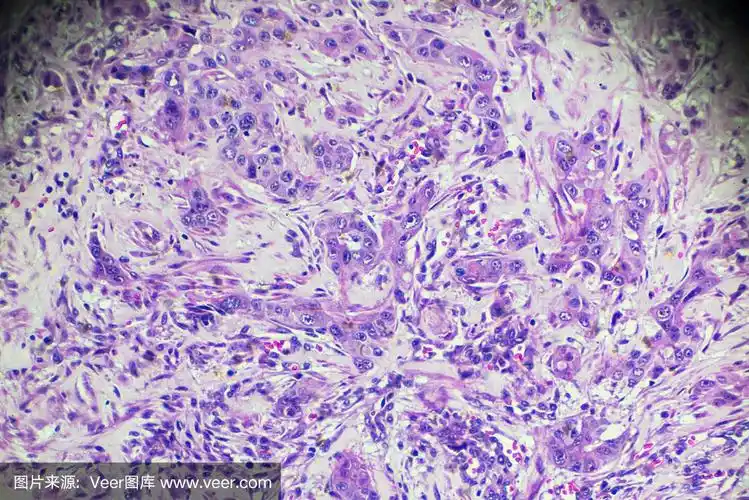

肝细胞癌,显微镜下的hcc

肝细胞癌镜下观